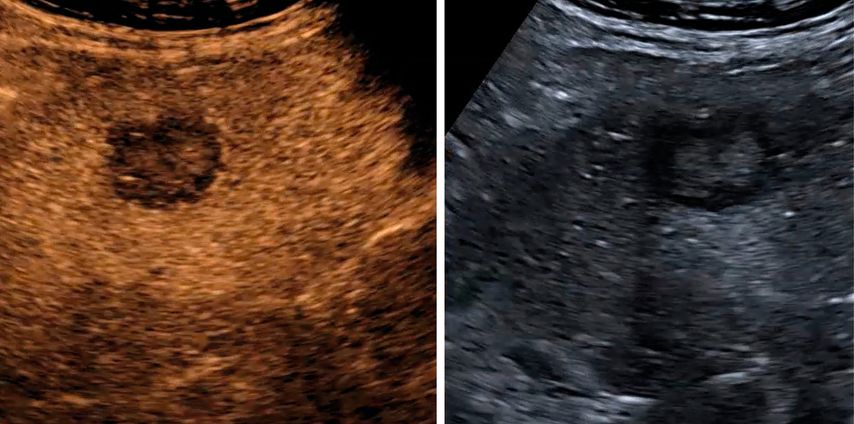

Trotz der hohen Aussagekraft moderner Ultraschallgeräte im B-Mode kann derzeit – mit Ausnahme des Screenings auf hepatozelluläre Karzinome bei chronischen Lebererkrankungen – kein generelles Leberscreening empfohlen werden.5 Die Mehrzahl fokaler Leberläsionen ist benigne, darunter fokale Steatosen, Zysten, Hämangiome oder fokale noduläre Hyperplasien (Abb.3). Maligne Raumforderungen sind in populationsbasierten Studien selten.6

Abb. 3: Darstellung einer fokalen nodulären Hyperplasie (FNH) in der arteriellen Frühphase nach Gabe von 1,2ml SonoVue® mittels CEUS (links) und in der mikrovaskulären Bildgebung (Canon®-superb „Microvascular imaging“-Modus), wo die Radspeichenstruktur besser zur Darstellung kommt

Mikrovaskuläre Bildgebung

Mit der Weiterentwicklung der Ultraschalltechnik hat sich in den letzten Jahren die mikrovaskuläre Bildgebung etabliert, welche die Darstellung kleinster Gefäße auch ohne Kontrastmittelgabe ermöglicht. Diese Verfahren nutzen spezielle Filter- und Signalverarbeitungstechniken, um langsame Blutflüsse von Gewebebewegungen zu differenzieren. Je nach Hersteller werden unterschiedliche Bezeichnungen verwendet, sie verfolgen jedoch das gemeinsame Ziel, die Beurteilung der Mikrovaskularisation zu verbessern und damit Diagnostik und Therapiekontrolle zu präzisieren.7